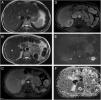

Esplenosis peritoneal múltiple simulando una metástasis mesentérica en una mujer con carcinoma mamario

Multiple peritoneal splenosis mimicking mesenteric metastases in a woman with breast carcinoma